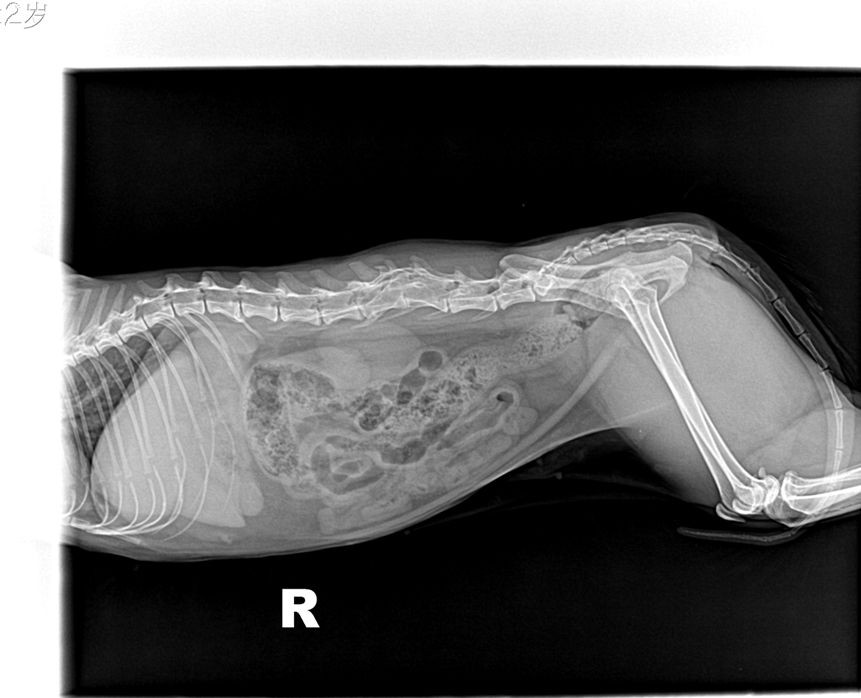

(2)识别X线影像中的颈椎、胸椎、腰椎和荐椎,并能确定属于位置(图6-12、图6-13)。

(3)识别椎间隙、椎间孔、棘突、横突的X线影像(图6-12、6-13)。

犬、猫正常脊柱由7节颈椎、13节胸椎、7节腰椎、3节荐椎和数量不定的尾椎连接而成。各椎骨间有椎间盘,但第1~2颈椎关节、3节荐椎之间无椎间盘。椎间盘由髓核和纤维环组成,呈软组织阴影,在X线片上表现为低密度的裂隙。邻近的椎间隙大致相等,但正常的第10~11腰椎椎间隙较狭窄。

犬椎体侧位投照显示似方形,多数脊椎可显示椎弓、椎管的背侧缘与腹侧缘、椎体前后端骨骺、棘突、横突和椎体。猫的椎体较长,侧位显示似长方形,椎弓根、关节突欠清楚,椎间孔背侧缘不如犬易见。棘突在腹背位投照时呈致密狭长的断面高密度阴影。侧位投照时,相连椎骨的大小、形状和密度大致相同。第2颈椎棘突靠近第1颈椎椎弓,或与之重叠。第6颈椎横突宽大,呈翼状。胸椎椎体长度略比颈椎椎体短。第11胸椎棘突垂直向上,称为直椎。直椎之前的胸椎棘突斜向后上方,而直椎以后的胸腰椎棘突则斜向前上方。后段4~5节胸椎的的关节后突下方、椎间孔的前上界处,可显示一细小、类三角形的副突阴影。